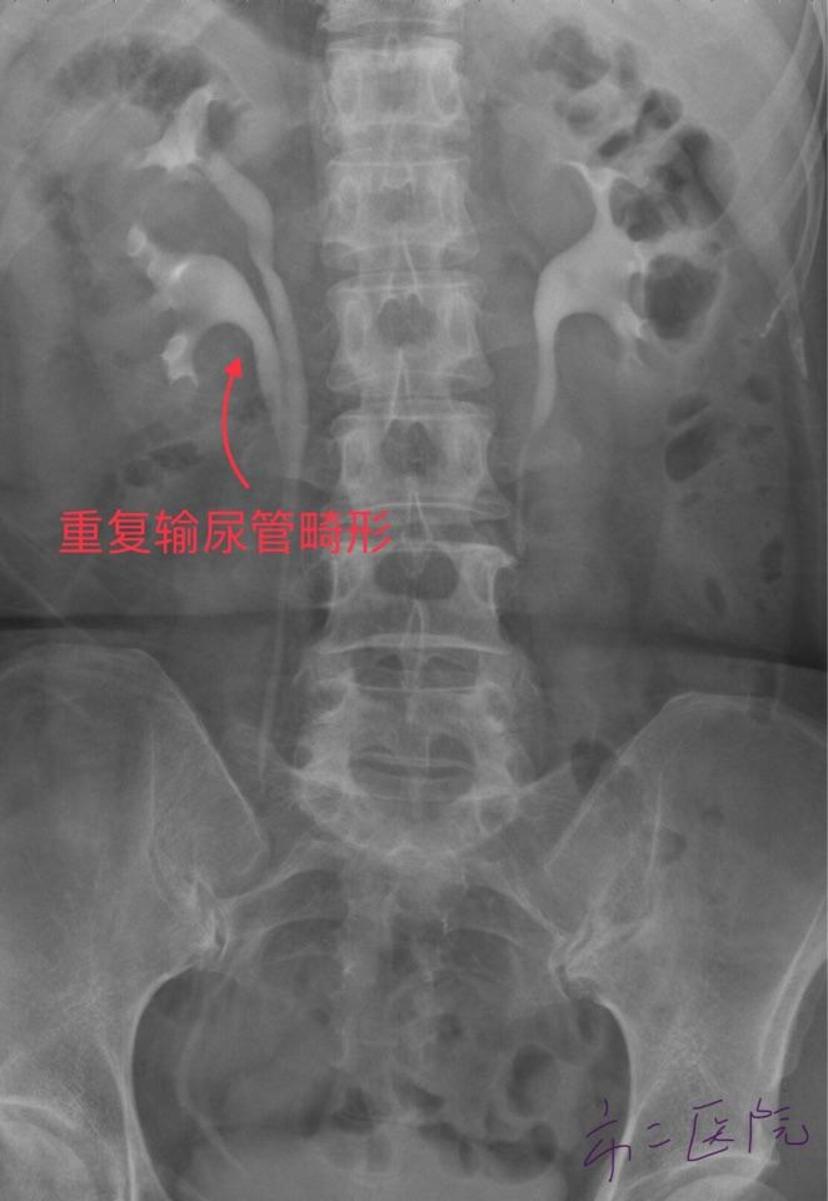

她腰部胀痛,尿频,尿痛2年,原来是"第三个肾脏"在作怪!